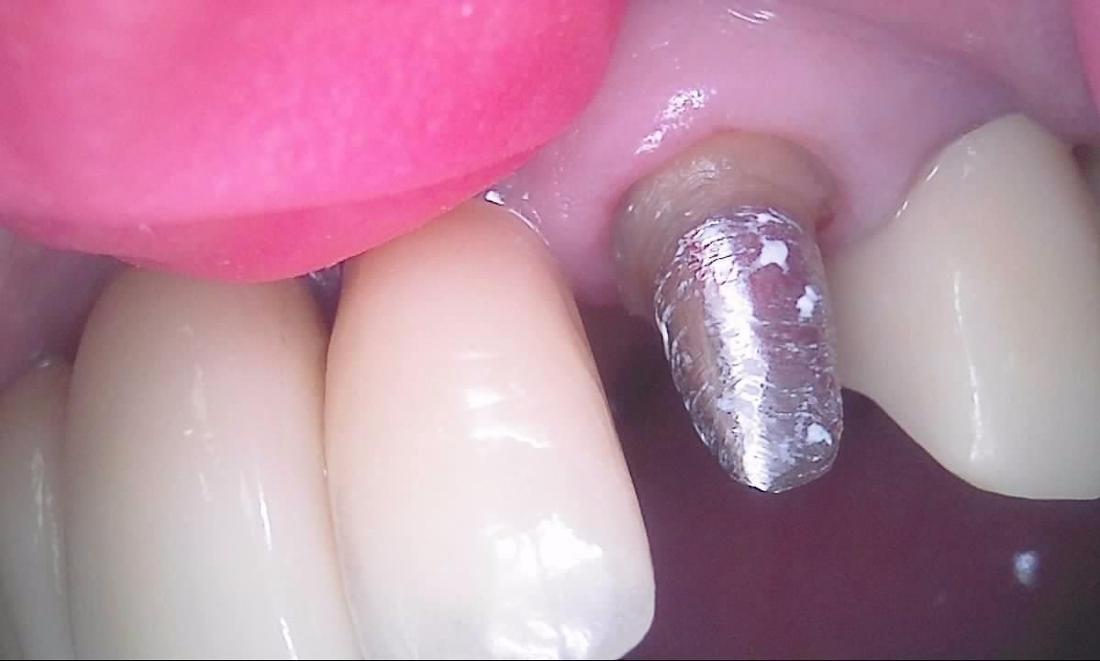

Here is an example of a tooth that had broken off at the gumline.  While people often think that every broken tooth must be pulled, in this case, we were able to do a root canal, followed by a cast post and core, and then cement a crown over the broken tooth.  This photo of the crown was taken seconds after it was cemented.  Root canals, posts, and crowns have been done for a very long time with a very good success rate, so saving teeth is always our first goal whenever possible.  We expect this tooth to have years and years of continued service.